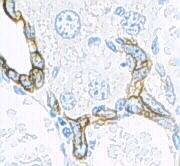

Furthermore, keratin expression is helpful in determining epithelial origin in anaplastic cancers. Tumors that express keratin include carcinomas, thymomas, sarcomas and trophoblastic neoplasms. Furthermore, the precise expression pattern of keratin subtypes allows prediction of the origin of the primary tumor when assessing metastases. For example, hepatocellular carcinomas typically expresse K8 and K18, and cholangiocarcinomas express K7, K8 and K18, while metastases of colorectal carcinomas express K20, but not K7.[25]